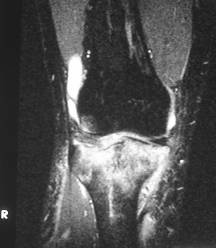

Bone bruise

n “microtrabecular” fracture

n No cortical break or instability

n Heals with rest

n Often associated with other injuries